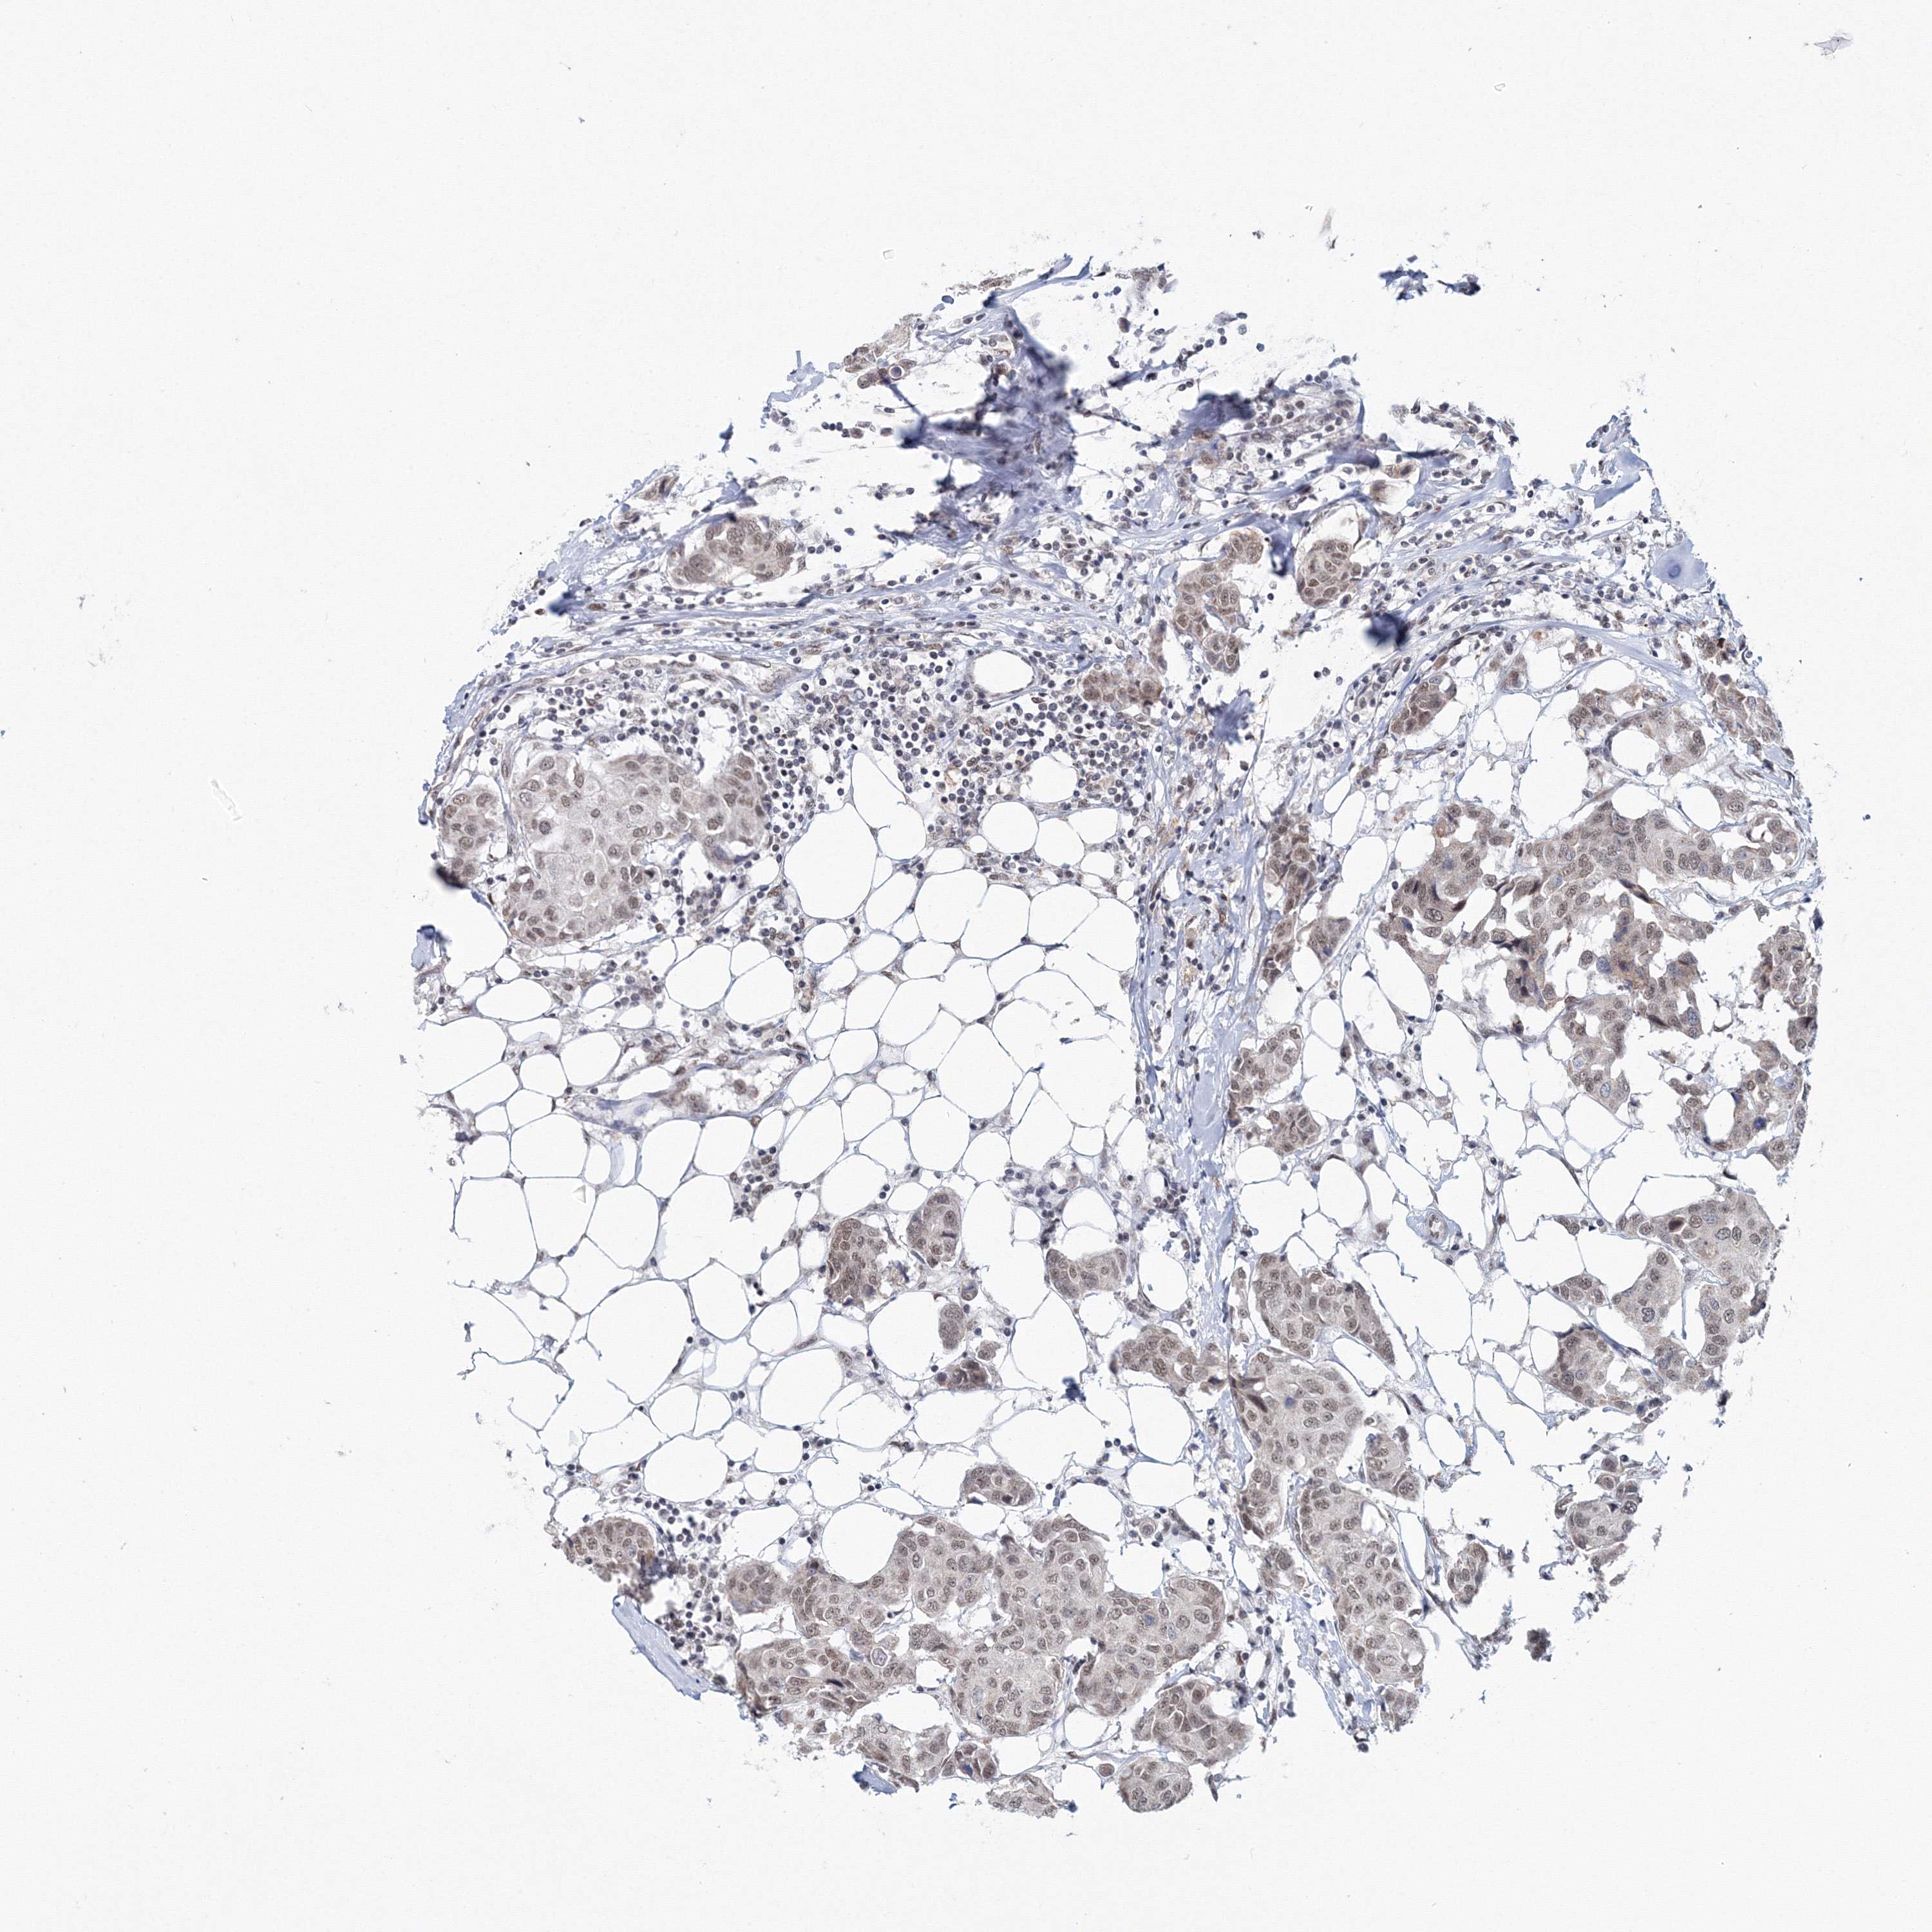

CANCER BREAST CANCER Show tissue menu

BRCA TCGA BRCA VALIDATION PROTEIN EXPRESSION

ANTIBODIES

AND

VALIDATION